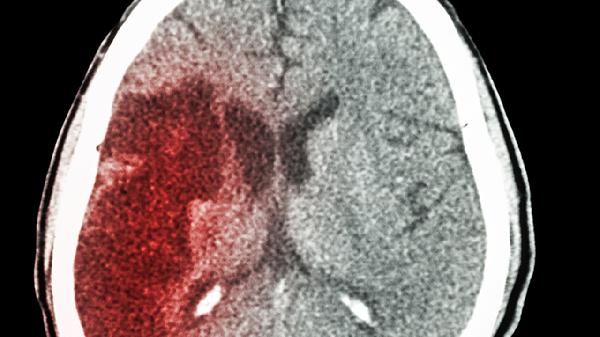

四十岁患者出现40毫升脑出血通常由高血压性脑出血、脑血管畸形、凝血功能障碍、长期吸烟饮酒、情绪剧烈波动等原因引起,可通过控制血压、手术治疗、纠正凝血异常、戒除不良习惯、心理疏导等方式干预。

脑出血恢复期需注意低盐低脂饮食,每日钠盐摄入不超过5克,多食用富含欧米伽3脂肪酸的深海鱼类。在康复医师指导下进行肢体功能训练,从被动关节活动逐步过渡到主动抗阻运动。保持规律作息避免熬夜,监测晨起和睡前血压并记录波动情况。定期复查头颅CT评估血肿吸收状况,出现新发头痛或意识改变需立即就医。心理康复同样重要,可通过参加病友互助小组缓解焦虑抑郁情绪。